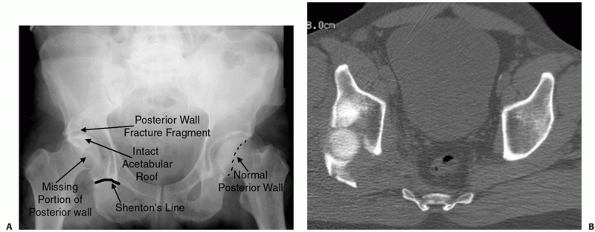

FIGURE 45-6 A.

Anteroposterior radiograph showing a dislocated hip on the right with the hip in neutral position. Radiographic signs of a posterior hip dislocation include a break in the Shenton line, proximal migration of the lesser trochanter, relatively smaller size of the affected femoral head (closer to the x-ray cassette), and a bony double density above the femoral head. The double density is the posterior wall fragment. It often sits atop the dislocated femoral head and can give the appearance of a normal joint space, potentially resulting in a misdiagnosis. B. Computed tomography shows a large displaced posterior wall fracture with the femoral head essentially fallen posteriorly through the posterior wall deficit. (Copyright Berton R. Moed, MD.) |